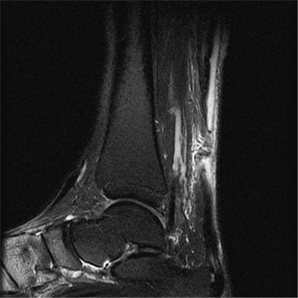

아킬레스건파열

아킬레스건 파열의 증상

1. 파열된 부분이 오목하게 들어감

2. 걷기는 가능하지만 발끝으로 설 수 없다.

x-ray 사진